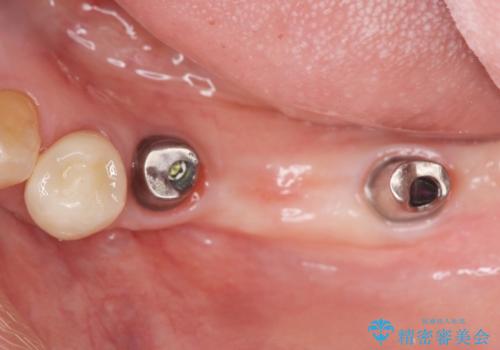

- 長年使っていた入れ歯をなくしてしまい、これを機にインプラントにしようと思い立ち来院されました。

通常長年インプラントを使用すると骨が吸収しインプラント治療が難しくなることもありますが、十分な骨が残っていたためすぐにインプラントの埋入計画を立てることができました。

- 113.3万円(インプラント×2・チタンカスタムアバットメント×2・ジルコニアクラウン×3・仮歯×3)費用は治療当時の料金となります